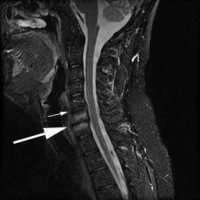

(Click to Enlarge Image) Normal cervical spine MRI. Arrow points to normal disc space. All the disc spaces are normal with good disc height and normal wall signal.